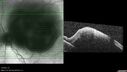

Ruptured Retinal Arterial Macroaneurysm - Submacular hemorrhage and BRAO

81 year old female with vision loss for a few days. Coumadin was high with INR at 3.1 VA 6/200